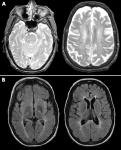

Neimann-Pick-ova bolest odnosi se na grupu naslednih metaboličkihporemećaja poznatih kao leukodistrofije ili poremećaji razgradnjelipida. Kod takvih bolesti dolazi do nakupljanja štetnih količina mastiu organima poput slezine, jetre, pluća, koštane srži i mozga.